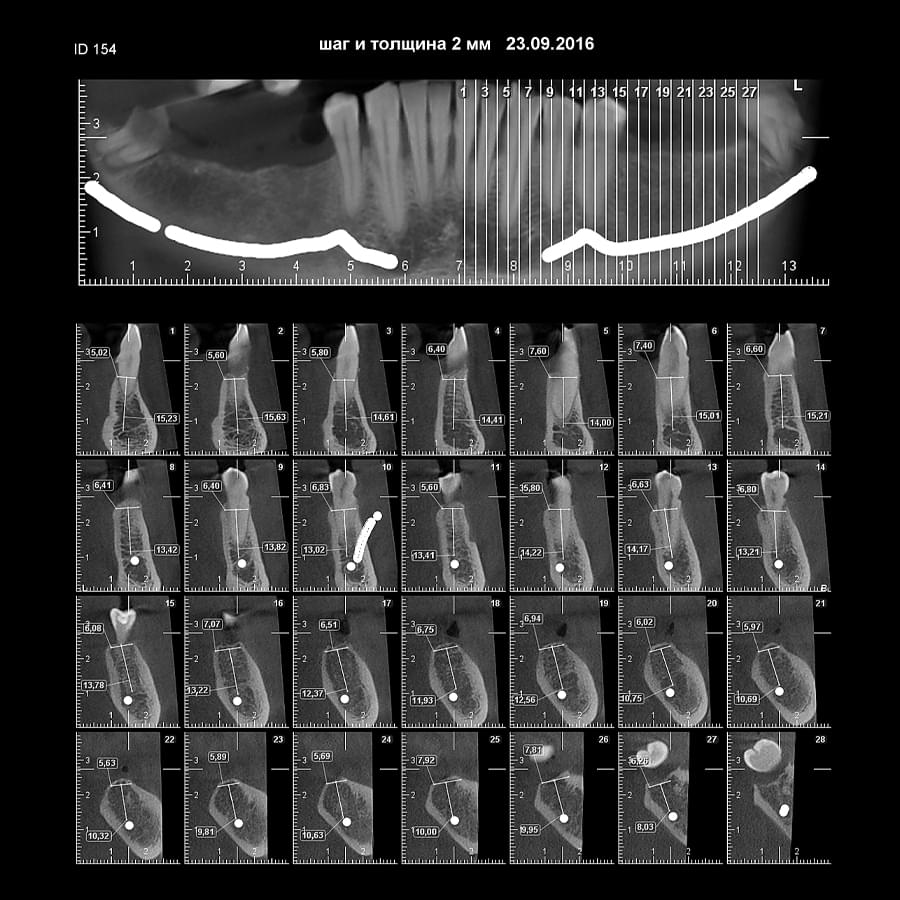

Візуальне порівняння (Кейс одного пацієнта)

Зуб — це не просто монолітний об'єкт, а складна система мікроканалів. На плоскому 2D-знімку вони часто перекривають один одного, створюючи ілюзію простої анатомії.

Непомічений канал — це джерело майбутньої інфекції та причина «загадкового» болю після лікування. Завдяки високій роздільній здатності обладнання MyRay, лікар бачить кожен мікронний канал ще до того, як візьме до рук інструмент.

Коли коріння «ховає сюрпризи» - Корені зубів часто мають складну кривизну, гачкоподібні закручення або розгалуження, які на звичайному 2D-знімку накладаються один на одного, створюючи ілюзію прямого каналу. На плоскій картинці неможливо побачити реальний об'єм та напрямок вигину, що критично важливо при видаленні «зубів мудрості» або ендодонтичному лікуванні. КТ MyRay дає змогу лікарю заздалегідь побачити 3D-геометрію кожного кореня, оцінити його близькість до нижньощелепного нерва чи гайморової пазухи та підібрати правильну тактику роботи. Це мінімізує ризики поломки інструменту в каналі або травмування сусідніх структур, перетворюючи складну хірургію на прогнозовану процедуру.